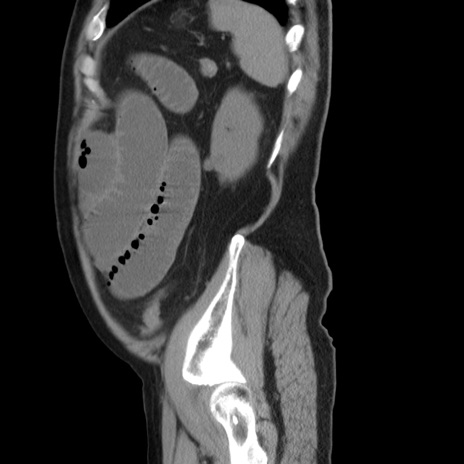

症例20(矢状断像)

【症例】 60歳代男性

【主訴】 腹部膨満、嘔吐

【現病歴】5日前頃より倦怠感を認め食事量減少し4日前の朝嘔吐、食事摂取困難となった。 3日前近医受診し点滴施行され整腸剤などを処方された。 当日他院を受診し、腹部膨満著明、炎症反応の上昇(CRP10.8、WBC11200)あり、紹介受診となる。

【身体所見】 意識JCS1 受け答えがはっきりしないBP 111/57mHg、 P 67bpm、、BT35.2°C、SpO2 97%(RA)、 腹部:膨隆、打診で鼓音あり、全体的に圧痛有り、腸蠕動音(-)、反跳痛ははっきりせず。

【データ】WBC 11400、CRP 14.20